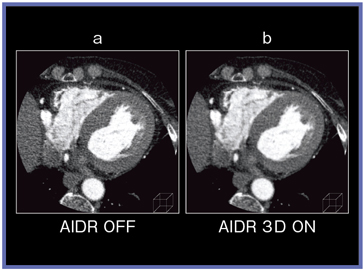

また,当院では,coronary CT angiography(CCTA)でも,積極的にAIDR 3Dを使用している。図5は,実効線量1.2mSv,1心拍でのCCTAであるが,AIDR 3D不使用(a)の場合はノイズが目立っている。一方で,AIDR 3Dを使用すると,実用レベルの画質を得ることができた(図5b)。さらに,AIDR 3Dを使用した小焦点での撮影では,空間分解能が向上しており,ステントや石灰化の描出が従来よりも明瞭となっている。プラークを定量的に評価するためのソフトウエアである“Plaque Viewing”でも,AIDR 3Dにより再現性の高いデータが得られるようになる。

![]() 図5 CCTAでのAIDR 3D使用によるノイズ低減 |